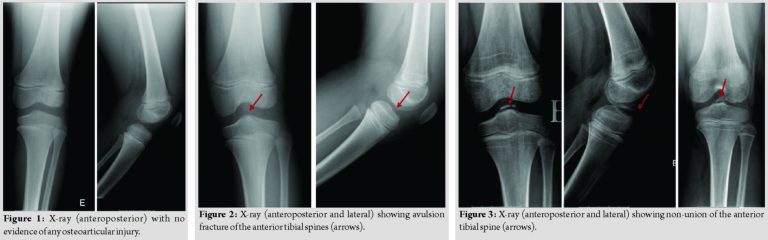

A 47-year-old Caucasian female, trader, with no relevant medical history, presented to the emergency department for pain in the proximal third of the left forearm, of sudden onset, intense, after movement of pronation, without a history of traumatism. She had no fever, no inflammatory signs, but she had pain on the palpation of the proximal radius and limitation of the active and passive mobilities. The radiographs of the elbow and forearm showed a pathological fracture of the proximal radius associated with lytic lesion (Fig. 1). Computed tomography (CT) scan of the left elbow showed “lytic lesion, with 57 × 18 mm, reduction and fragmentation of cortical thickness –a pathological fracture; without suspected reaction of the periosteum” (Fig. 2).

An immobilization of the left arm and forearm was performed. The magnetic resonance imaging of the left forearm revealed “primary bone lesion without invasive features of the soft tissues that can correspond to aneurysmal bone cyst or GCT” (Fig. 3). A biopsy and surgery were proposed. The patient underwent excision and curettage of the lesion with preservation of the periosteum, filling with the left proximal (corpse) allograft and osteosynthesis with plate and screws (Fig. 4).